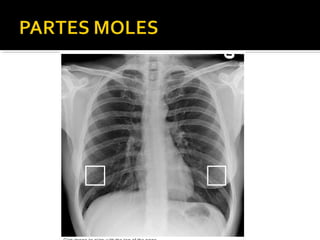

Este documento fornece parâmetros técnicos para realizar uma radiografia de tórax, incluindo posicionamento correto do paciente, dose adequada de radiação e estruturas anatômicas a serem avaliadas, como coração, pulmões, pleura, diafragma e ossos do tórax.